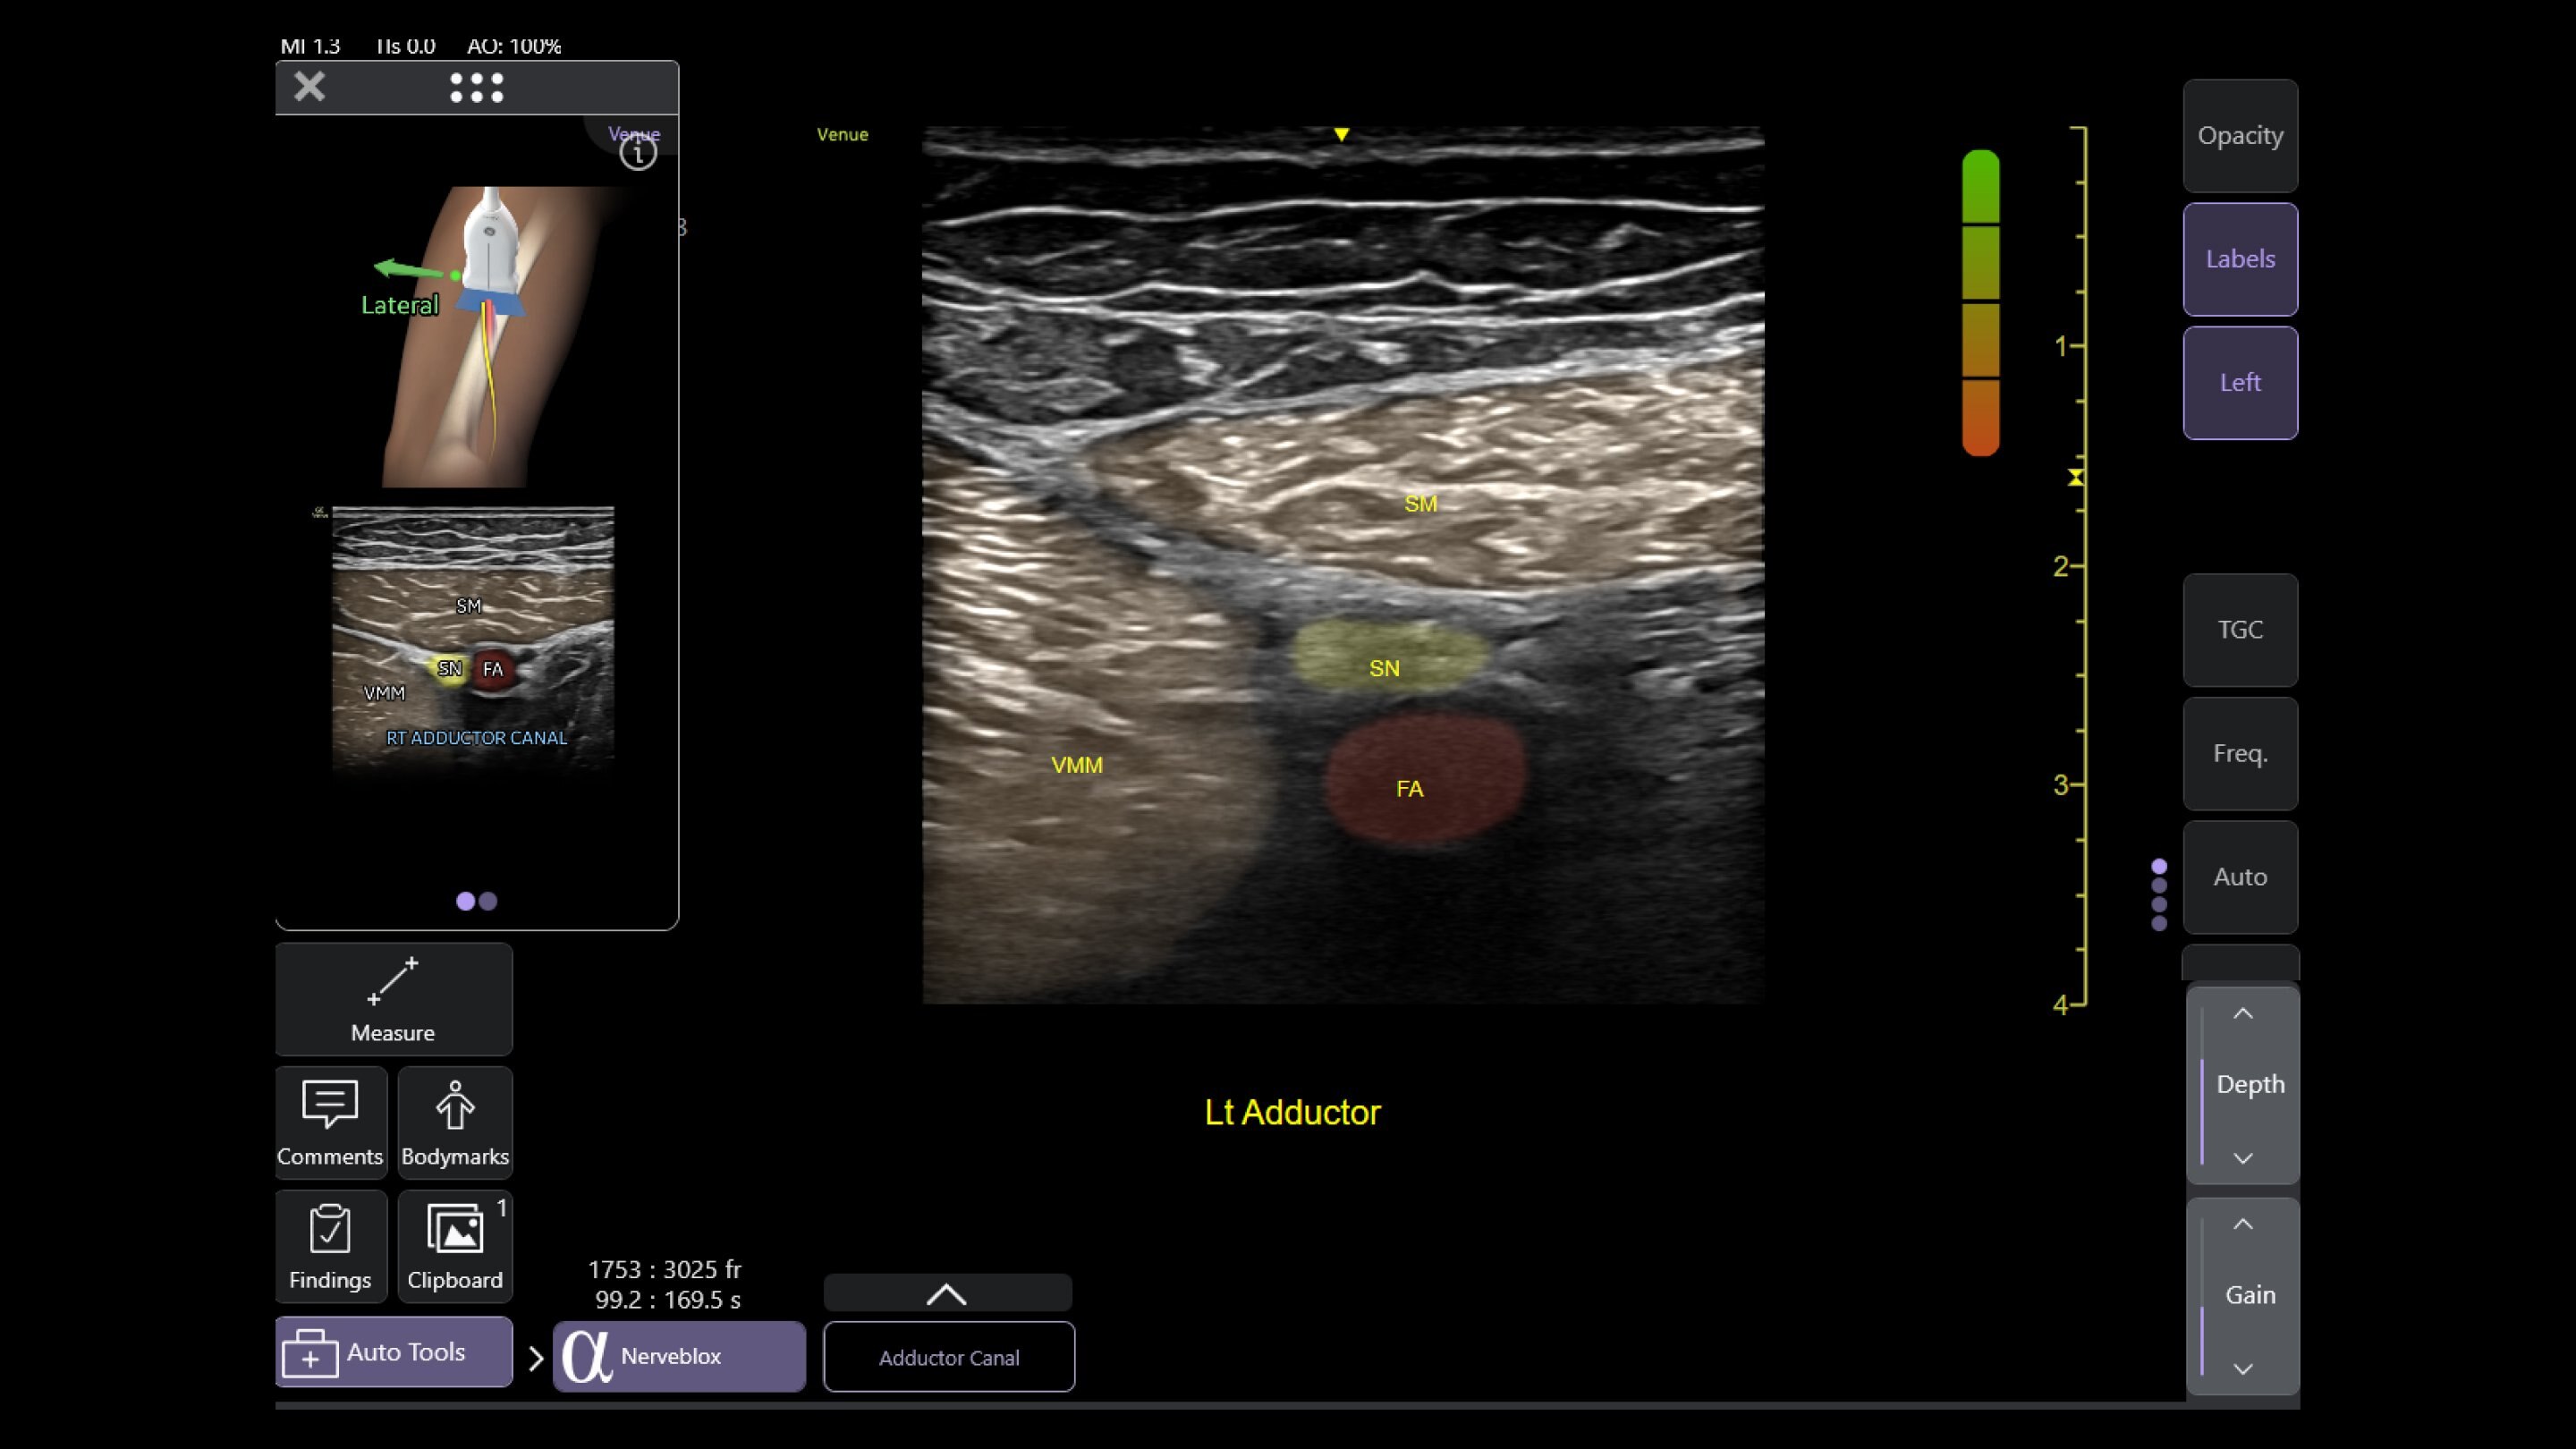

幅広い機能を搭載、多彩な用途に活用できるポイントオブケアエコーシステム